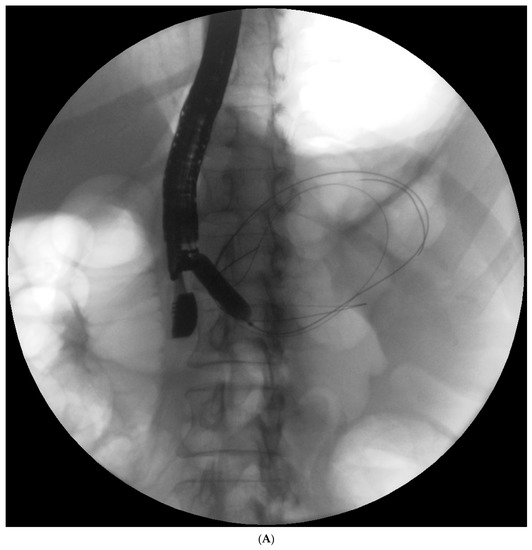

Endotherapy for post-inflammatory pancreatic and peripancreatic fluid collections (Figure 1A–L) is a recognized, minimally invasive treatment method [6][7][8]. Transpapillary endoscopic drainage involves accessing the collection through the major duodenal papilla if the main pancreatic duct communicates with the collection [6][10][11][12][13]. Active transpapillary drainage involves the introduction of a nasal drain and a pancreatic stent through the major duodenal papilla with their distal ends passing through the site of disruption into the lumen for the fluid collection [6][10][11][12][13]. Subsequently, the collection is rinsed with a saline solution through the drain. Passive transpapillary drainage involves the introduction of a stent into the main pancreatic duct, which is important for endotherapy for main pancreatic duct disruption [6][10][11][12][13]. The size and length of the pancreatic stent should be selected individually according to the fluoroscopic image of the main pancreatic duct during endoscopic retrograde pancreatography. Main pancreatic duct stenting (passive transpapillary drainage) is designed to ensure the free outflow of pancreatic juices by physiological means into the duodenal lumen and, consequently, to prevent the juices from escaping through the injured duct into the collection, thus increasing its volume. Moreover, inserting a stent into the pancreatic duct (Figure 2A–C) is supposed to create conditions that promote healing and stop pancreatic juice leakage by bridging the disrupted part of the duct.

Figure 1. (A–L) Endoscopic treatment of walled-off pancreatic necrosis. In the second week of acute necrotizing pancreatitis, the acute necrotic collection (A) is visible in the abdominal contrast-enhanced computed tomography (CECT), which evolved in the sixth week of the illness duration into the symptomatic walled-off pancreatic necrosis (B). Patient qualified for endoscopic treatment (C–F) transmural drainage using the self-expanding metal stent (C,D) and endoscopic necrosectomy (E,F) was performed. In the second week of endotherapy, the endoscopic retrograde pancreatography (G–J) was performed. During pancreatography, the complete pancreatic duct disruption was stated (G–I) and transpapillary drainage was carried out (J). After achieving the treatment’s success and the complete regression of the necrotic collection, the transpapillary stent was observed in the bottom of the collection via the endoscopic view from the stomach’s side through the transmural stent (K). Control CECT confirmed the total regression of the collection (L).

Figure 2. (A–C). Endoscopic treatment of the pancreatic pseudocyst. Transmural drainage using plastic stents was performed (A,B). The endoscopic retrograde pancreatography (C) was performed. During the pancreatography, complete disruption of the pancreatic duct was stated (C). Transpapillary access to the pseudocyst was achieved (C). Transmural access to the same collection was stated (A,B).